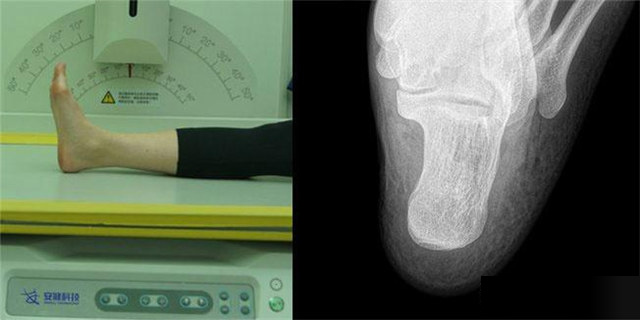

下肢:胫腓骨、踝、足胫腓骨长骨检查需要包括--侧的关节踝关节常规正+外侧位,特殊时可选内斜位足常规前后正位+内斜位,外伤鉴定等情况,需要负重的水平侧位(包括足尖和足跟)跟骨侧位+轴位